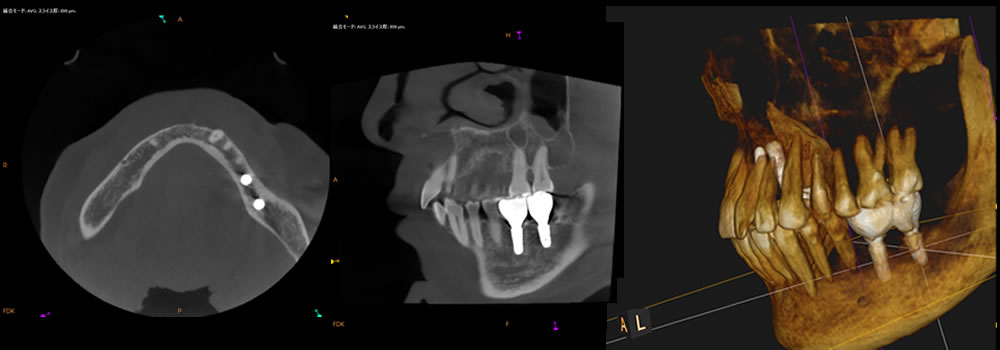

患者さまと相談し、インプラント治療と矯正治療によって咬合状態を改善する計画を立てました。左下奥歯は、歯のない期間が長く、顎骨が退縮していたため、インプラントの埋入時に骨造成を併用して骨を再生することにしました。

左下奥歯にインプラントを埋入した後のCT画像です。骨造成によって骨が再生し、インプラントが安定しています。